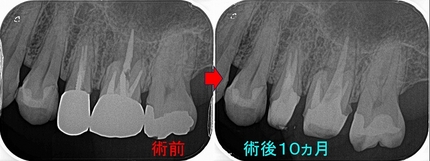

クラウンが取れた歯の根管治療

基本的に私は歯を長持ちさせる為のポイントは「必要最小限の医療介入」だと思っています。

を過去に取った歯のクラウンのやり替えの際には、根尖病変さえ無ければわざわざ根管治療はしません。

患者さんは30代女性

昔から診させて頂いているかんじゃさんなのですが、被せ物が外れたということで来院

過去からのレントゲンを見ると

2025 EEdental FRI (1).jpg

口蓋根の根尖に前は無かった根尖病変が現れています。

患者さんに、レントゲンを見せてクラウンだけ入れてもまたすぐに外す必要が出てきそうだから

この歯に関しては一度根管治療からやり直した方がいいと説明

術後

2025 EEdental FRI (2).jpg

4根ガッタパーチャー使用 レジンコア+仮歯まで

定期検診で来院してもらいました。

2025 EEdental FRI (3).jpg

綺麗に口蓋根の根尖病変は治ってくれています。

ついでに返信投影でレントゲンを撮らせてもらいました。

2025 EEdental FRI (4).jpg

綺麗に治ってくれたので、次にセラミッククラウンの治療に入って行きます。

このように根管治療に介入するしないは、私の場合病変のある・なしで判断することが殆どで

前の先生の治療が信用でいないとか、ガッタパーチャーが入っていないからという理由で根管治療をやり替えることは殆どありません。

根管治療は2回しか治療出来ない治療なので、歯を長く保存させるにはいつ根管治療介入に踏み切るか!?も重要なポイントだと思います!(^。^)